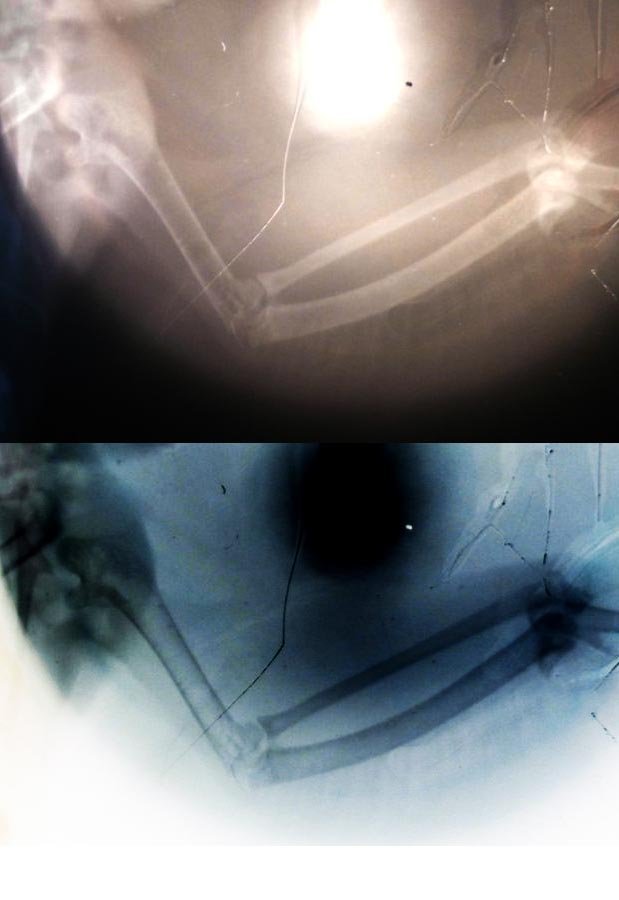

Zosia Опубликовано 25 апреля, 2019 #46 Опубликовано 25 апреля, 2019 вот поиграла в фотошопе- все видно хорошо

Demonit Опубликовано 26 апреля, 2019 Автор #66 Опубликовано 26 апреля, 2019 Если пальчик отомрёт - насколько это плохо? Подозреваю, что лечение нужно начать как можно быстрее, но судя по всему оно начнется только завтра. Нашел только пару мест, где одновременно можно купить Травматин и Артрогликан, и то о точном наличии можно будет узнать только завтра (я сам администратор интернет-магазина и знаю, что отображение фактического наличия - это сильно дорого). Пока решаю вопрос с "человеческими" препаратами, утолите любопытство) 22 часа назад, Zosia сказал: вот поиграла в фотошопе- все видно хорошо Где видно?) Возможно мне даже как-то поможет в реабилитации.

Zosia Опубликовано 27 апреля, 2019 #84 Опубликовано 27 апреля, 2019 По поводу артрогликана. Надо крыло подстричь, самофиксирующим пластырем уложить в анатомически правильном положении. После чего начинать артро, по 1/6 таблетки в сутки, 3 недели. Через 3 недели- контрольный рентген.